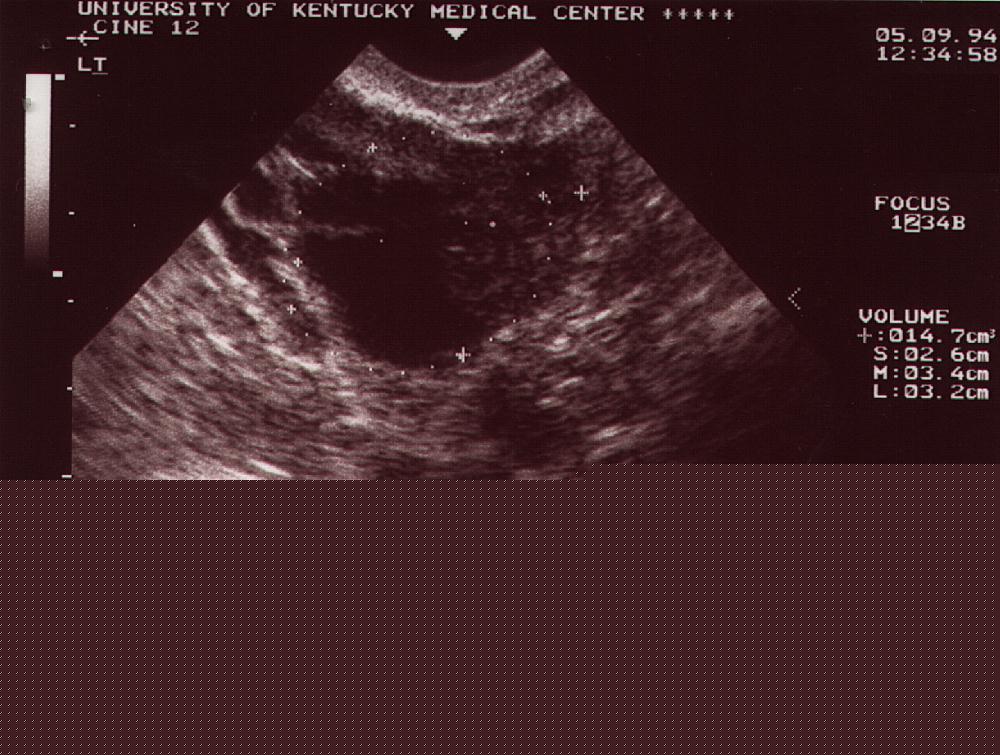

| TVS size, cm3 |

14.7 |

| TVS – cystic |

+ |

| TVS – septation |

| TVS – MI |

6 |

| Tumor Stage |

IA |